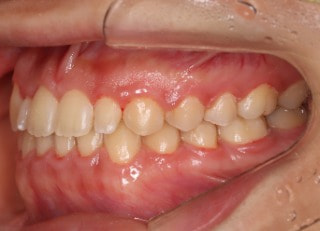

治療開始から25ヶ月後